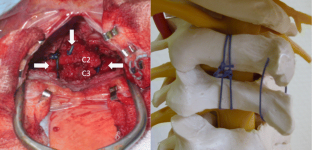

Via a posterior midline approach, the lamina of C2 and C3 was conflated in a modified sublaminar wiring technique using non-resorbable sutures, sparing the ossification zones of the vertebral arches. Postoperative immobilization in a halo vest facilitated bony fusion of the laminae at C2/3 without lordotic displacement of the cervical spine.